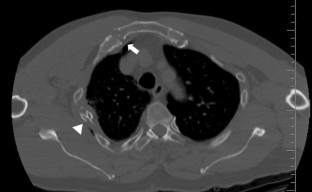

Fig. 1

Fig. 2

Fig. 3